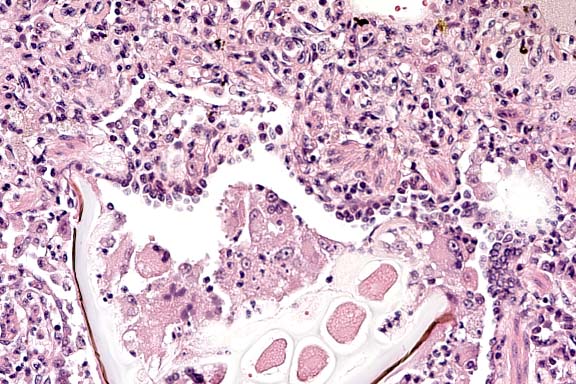

Case 27-4a. Lung. A bacterial colony and many neutrophils are plugging a small artery. and the neutrophils are transmigrating the vessel wall (bacterial embolus with necrotizing vasculitis) into the adventitia and interstitium. 40X

1. Multifocal, suppurative, pulmonary vasculitis and thrombosis with intralesional gram positive cocci.

2. Multifocal, granulomatous pneumonia with birefringent foreign material.

3. Acute, multifocal, perivascular interstitial pneumonia.

Critical features to the development of the lesions in this monkey were the jugular catheter and the epididymitis. The catheter may have injured the right atrioventricular valve, predisposing to the vegetative endocarditis and it may have also provided the source of the sepsis. Another likely source of the sepsis was the epididymitis. Injury to the endothelium is critical to the establishment of endocarditis but Staph. aureus can implant on previously "normal" valves. Bacterial emboli released from the right atrioventricular valve showered the lungs and caused an embolic pneumonia and vasculitis. A second lesion in the lungs of this monkey was the multifocal granulomatous pneumonia. This may have been the result of inhalation of foreign material during a period of illness or perhaps during one of the anesthetic procedures. Birefringent foreign material is present in the giant cells and a second type of foreign material is seen in the larger airways and is more consistent with plant or food material. Other birefringent material noted in the lungs is "mite exhaust" and acid hematin (artifact).

1. Lung: Pneumonia, necrosuppurative, embolic, multifocal, moderate, with necrotizing vasculitis, fibrin thrombi, and numerous cocci, rhesus monkey (Macaca mulatta), primate.

2. Lung: Bronchopneumonia, granulomatous, multifocal, moderate, with foreign material.

Conference Note: Conference participants discussed the importance of recognizing that two distinct processes are evident. One process is chronic, bronchocentric, and a result of foreign material introduced into the airways. The other process is more acute, angiocentric, and a result of staphylococcal bacteremia.